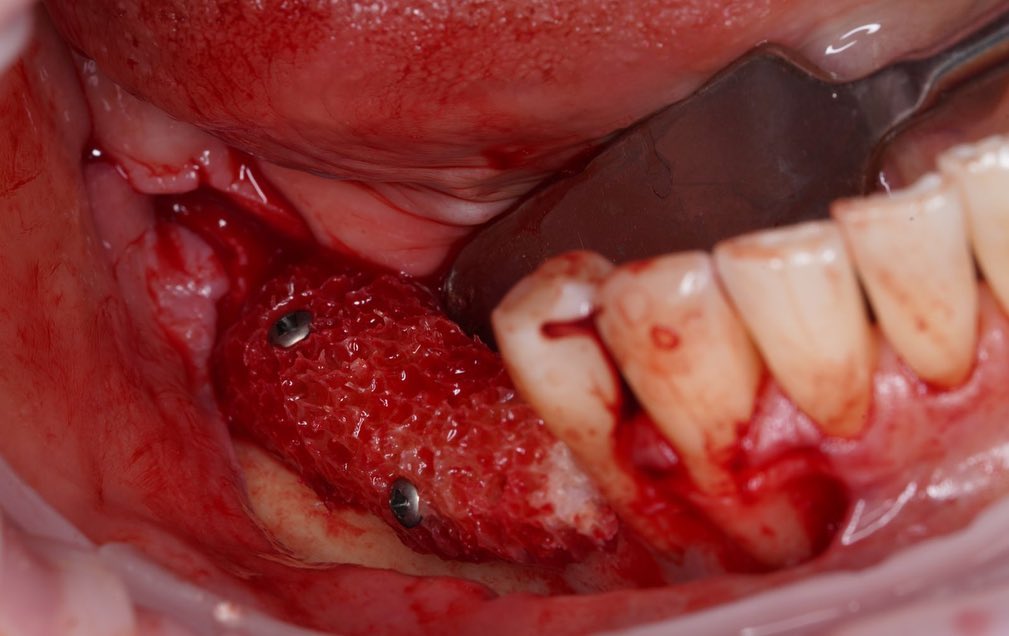

Проведена направленная костная регенерация жевательной группы зубов с использованием костного заменителя и мембраны.